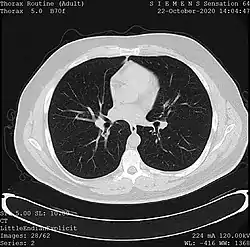

One frame of a CT scan of the chest showing the heart and lungs | |

- X-ray computed tomography (CT), or Computed Axial Tomography (CAT) scan, is a helical tomography technique (latest generation), which traditionally produces a 2D image of the structures in a thin section of the body. In CT, a beam of X-rays spins around an object being examined and is picked up by sensitive radiation detectors after having penetrated the object from multiple angles. A computer then analyses the information received from the scanner's detectors and constructs a detailed image of the object and its contents using the mathematical principles laid out in the Radon transform. It has a greater ionizing radiation dose burden than projection radiography; repeated scans must be limited to avoid health effects. CT is based on the same principles as X-Ray projections but in this case, the patient is enclosed in a surrounding ring of detectors assigned with 500–1000 scintillation detectors[13] (fourth-generation X-Ray CT scanner geometry). Previously in older generation scanners, the X-Ray beam was paired by a translating source and detector. Computed tomography has almost completely replaced focal plane tomography in X-ray tomography imaging.